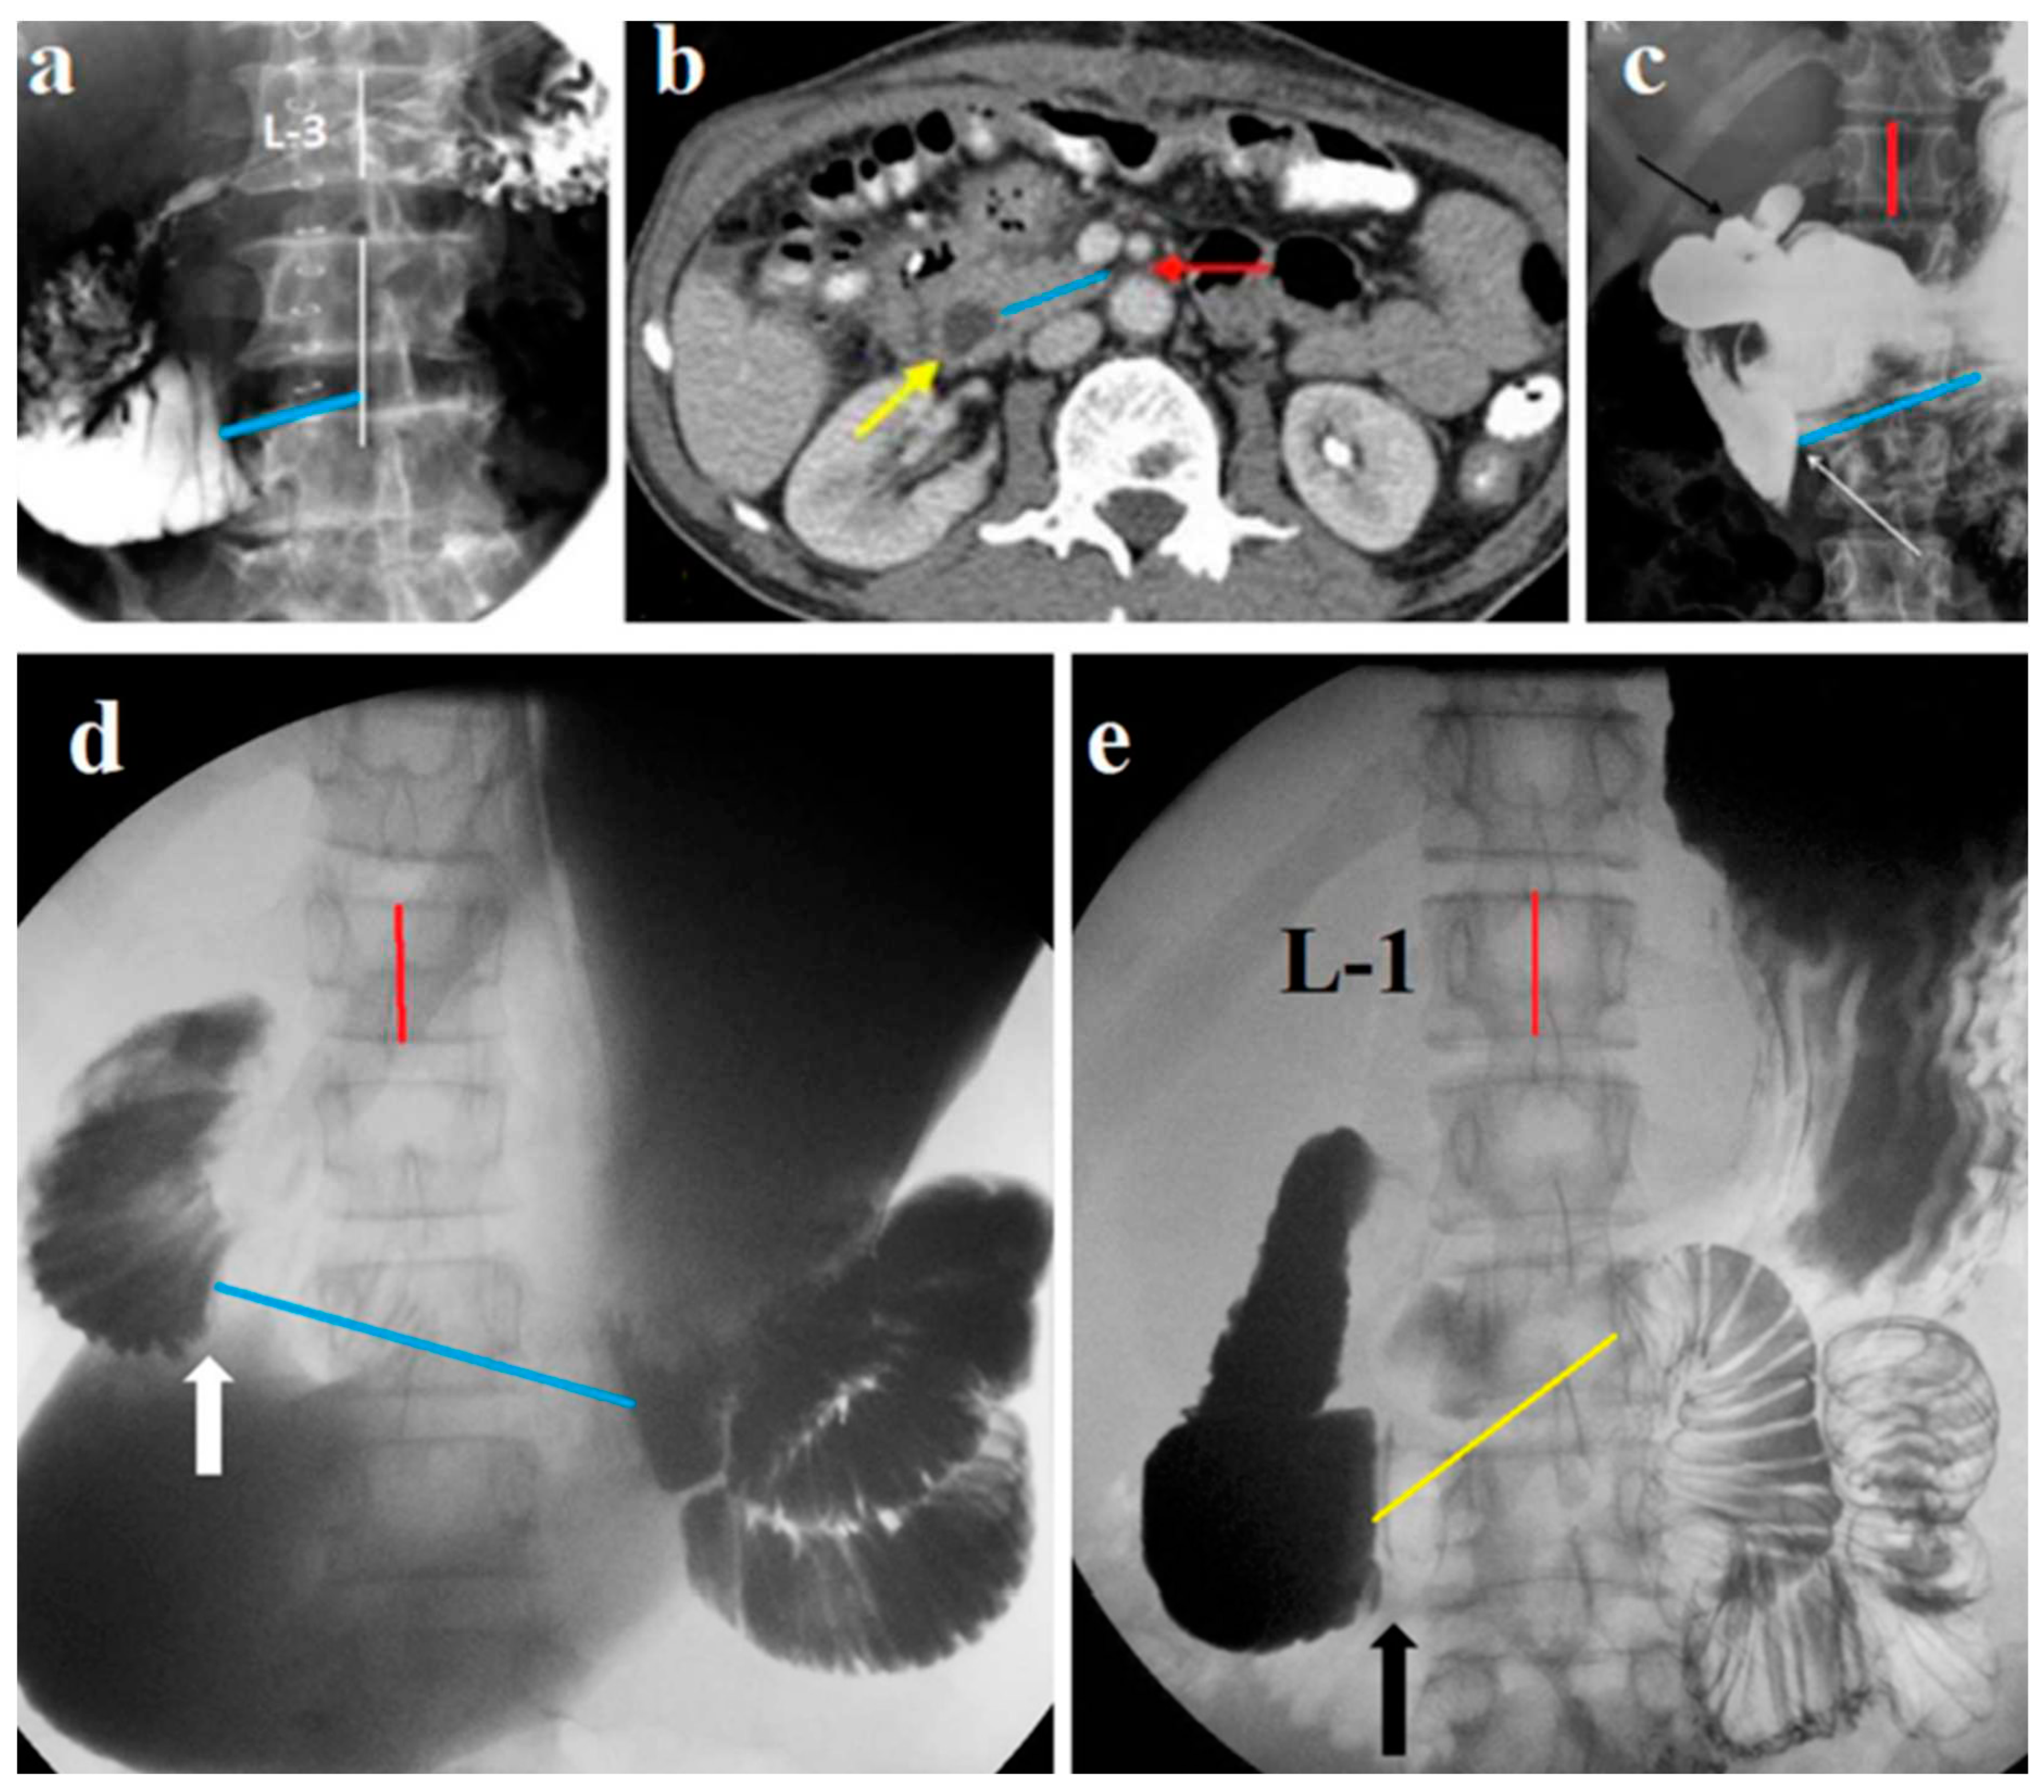

22] due to dyskinesia of the duodenal sphincters. The radiological criteria of the SMAS, described by the authors are typical signs of duodenal dyskinesia: 1) gastroduodenal dilatation with delayed gastric and duodenal emptying is absent in the typical example of SMAS presented by the authors (

Figure 6a), (2) abrupt vertical or oblique cutoff of contrast shadow at the third part of the duodenum is due to contraction Ochsner's sphincter, (3) 'to and fro' flow of contrast between Ochsner's and Kapandji's sphincters is also known as pendulum-like movement of contrast agent, is normal reaction to acid. In none of the described observations was there a sharp dilation of the stomach and duodenum with a clinical picture of intestinal obstruction. An analysis of the article by Kim et al shows that the authors examined patients with hypersecretion of hydrochloric acid with special attention to the condition of the duodenum. Ignoring the clinical symptoms, in mild cases they called them “without SMAS”, and in more severe cases of duodenum dyskinesia they called them “with SMAS”.

Caterine et al retrospectively evaluated radiographs of patients with weight loss, reflux, and dysphagia. They believed that a radiological conclusion about SMAS is possible with a combination of three criteria (1) dilation of the first and second parts of the duodenum; (2) abrupt vertical or oblique mid-to-left of midline compression of the third part of the duodenum; and (3) “to-and-fro” flow of contrast proximal to the compression. The authors believe that radiological signs are often incorrectly assessed due to an anatomic impression by the inferior vena cava to the right-of-midline. There were 5 patients who had a clinical diagnosis of SMAS which was identified in their patient notes. None of the patients with a clinical diagnosis of SMAS radiological criteria for SMAS. All five patients had a right-of midline duodenal impression, and not where the superior mesenteric artery is located (

Figure 6b).

Figure 6.

Radiographs of the stomach and duodenum in patients with peptic symptoms.

(a). X-ray from the article by Kim et al with a conclusion about SMAS [

21]. Although the proximal part of the contracted Ochsner sphincter is in the middle of L-3, the stomach and proximal part of the duodenum are not dilated, indicating sufficient cross-country ability of the duodenum.

(b). X-ray from an article by Caterine et al with a clinical diagnosis of SMAS [

23]. However, the long, narrow section of bowel to the right of the spine cannot be caused by compression of the SMA. The stomach and duodenum are not dilated and there are typical radiological signs of gastritis and duodenitis.

(c-d). Studies from the article by Oka et al [

25] supposedly confirm the diagnosis of SMAS.

(с). On the radiograph, the intestine begins to contract 3.5 cm to the right of the AMA (blue line).

(d). In the axial view of CT, the length of the contracted portion of the duodenum is 4.5 cm (blue line) to the right of the AMA.